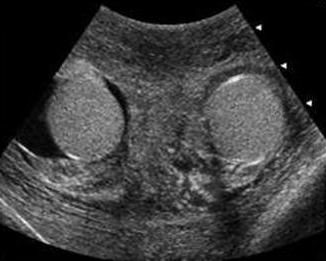

Scrotal

The Scrotal ultrasound application creates reports for diagnosis of male reproductive organ findings. Measurements flow from the modality to allow reporting of both quantitative and qualitative findings.

- Groin, scrotum, epididymis, cysts, testicles and masses